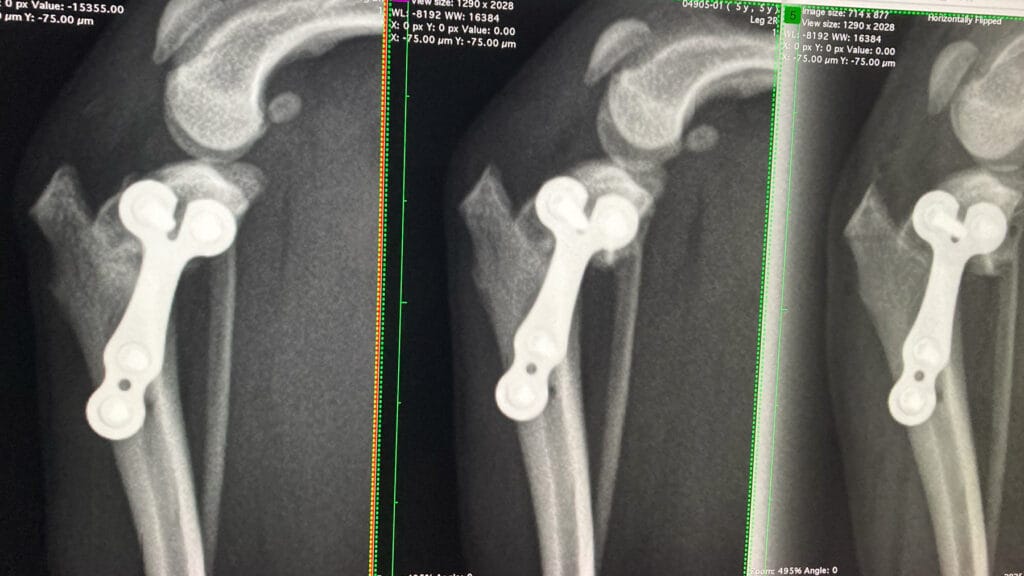

脛骨高平部水平化骨切り術:TPLO

TPLOは小型犬から大型犬にも対応できる強力な術式です。

本来傾斜のある脛骨高平部を骨切りし回転して水平にすることで、 体重をかけた時に大腿骨と脛骨がズレないようにする術式です。

レントゲンのように、大腿骨(太ももの骨)と脛骨(すねの骨)が正常な位置にもどされ、体重をかけても大丈夫なようになりました。

今回のような小型犬でも小さなプレートを用いることで、手術は可能です。

TPLO(脛骨高平部水平化骨切り術)、ATT(脛骨粗面前進化術)、または古くからの術式である関節外方(ラテラルスーチャー術)のどれを選ぶかは、飼い主様と話し合いのもと決めていきます。

滑車溝造溝術

滑車造溝術(ブロックリセッション):大腿骨滑車溝を深く形成することで、膝蓋骨が脱臼しづらくなっています。

側面からの撮影